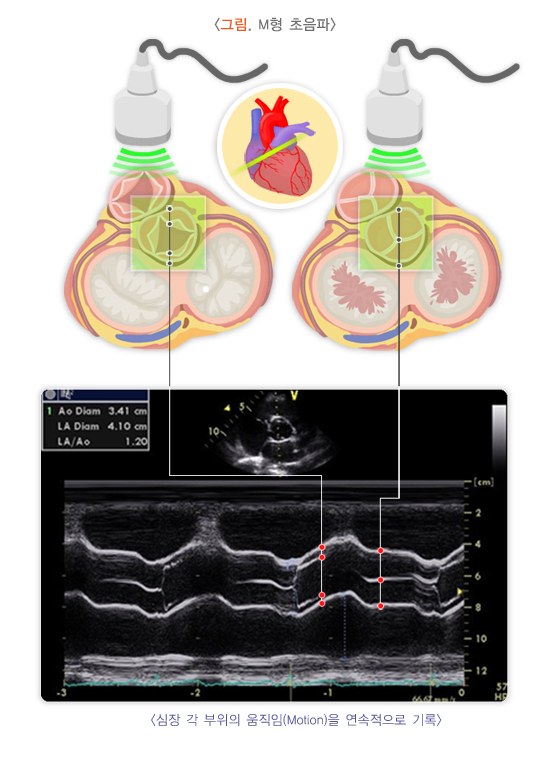

3. M형(motion mode) 심초음파

일직선으로 초음파를 보내며, 그 선상에 놓여 있는 조직에서 반사되는 초음파를 심장의 주기에 따라 연속적으로 기록합니다. 주로 각 구조물의 두께와 깊이 등을 측정하는 데 유용합니다.